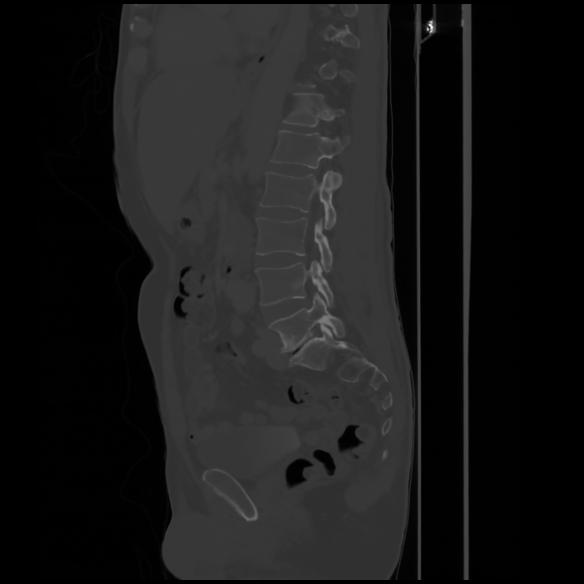

7 CUERPO,CE,Sagittal,3.000,CUERPO,Sagittal,